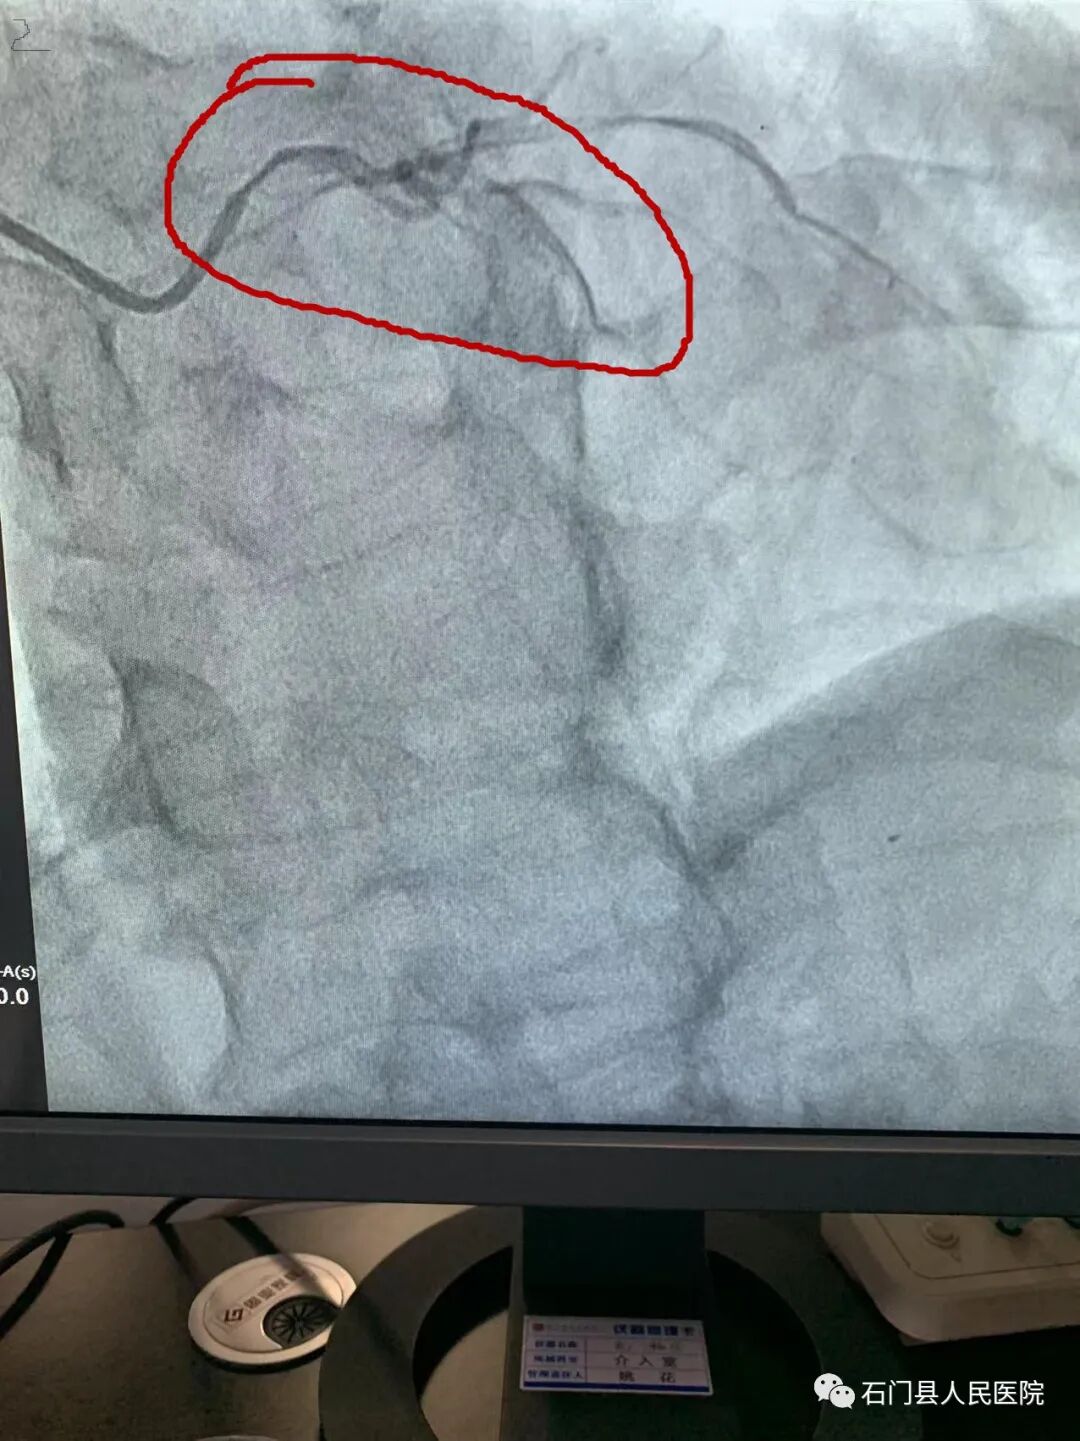

经桡股动脉冠脉造影术、支架植入术、球囊扩张术、主动脉支架置入术,心脏永久起搏器植入术、心脏射频消融术;房间隔缺损封堵术,左心耳封堵术。